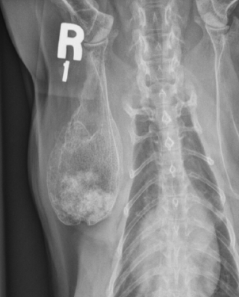

별놈의 지방종, 고양이 견갑골 뼈속부터 지방종?

제목에 딱 박힌 Rare 하다는 말. 그냥 신기한 구경정도로 생각하는게 좋을듯 하다.

양성 종양이지만 뼈를 파괴할 수 있다는 교훈 정도는 기본으로 가지고 가야 할듯 하다.